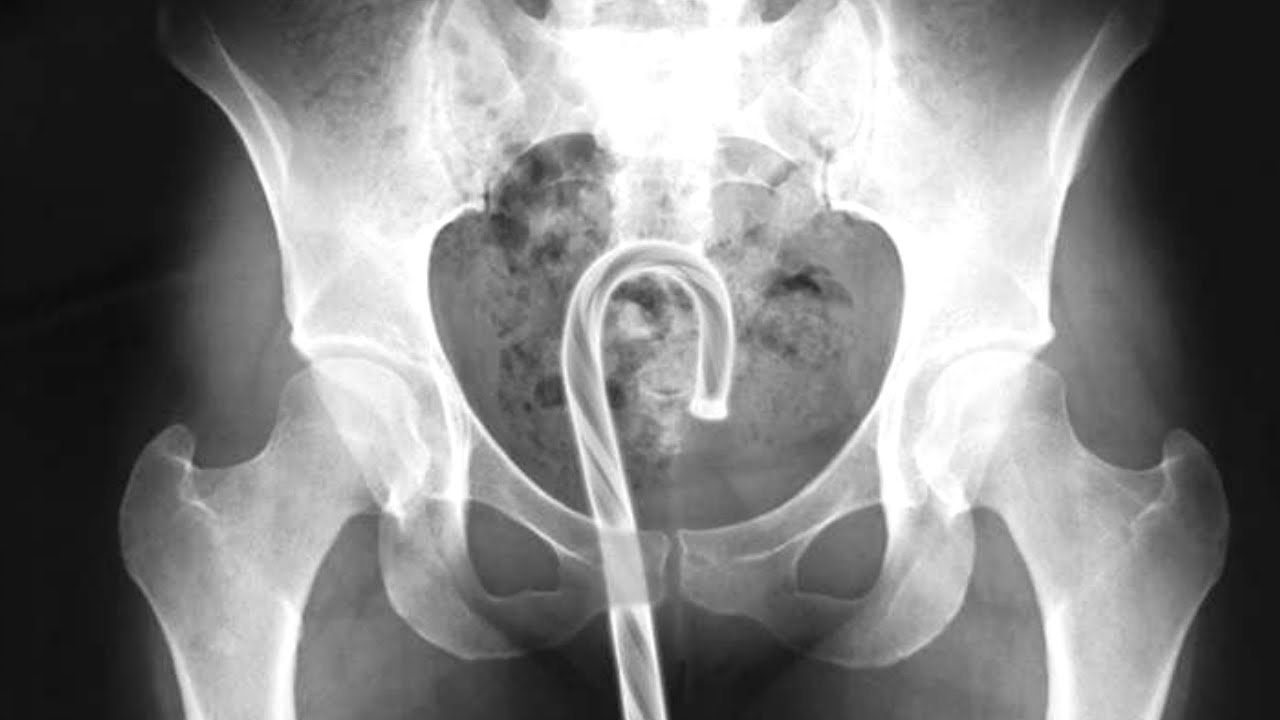

Strange object 01.jpg Strange object 02.jpg Strange object 03.jpg Strange object 07.jpg Strange object 10.jpg Подборка странных предметов, обнаруженных в человеческом теле. Пожалуй, элемент смешного присутствует ))) Хотя "носителям" вряд ли до смеха. )) Впрочем, кто им виноват?